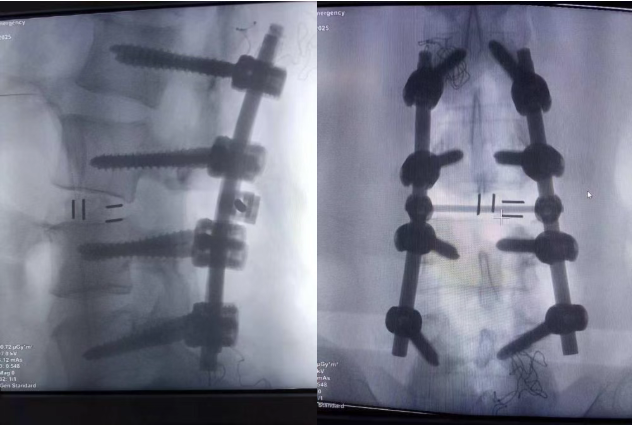

“复杂脊柱骨折的关键是‘精准’”,陈钢表示:“既要复位骨折,又不能碰伤神经,每一步都像拆炸弹。”患者的腰3/4椎体已经完全错位,硬膜内的神经已经极度受压扭曲,团队必须在保护神经的前提下,快速完成复位。陈钢带领团队采用安全有效复位技术,将脱位的腰3/4椎体精准复位,并用钉棒固定,同时小心翼翼地清除压迫脊髓的骨块,避免进一步损伤神经,实现了腰椎的复位与脊髓压迫的解除。整个手术仅耗时2个多小时,出血控制在400毫升以内,并利用自体血回输,珍惜用好每一滴血液。

手术中骨折脱位已经复位